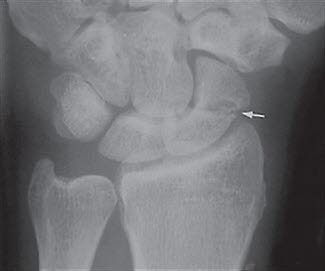

Etter skaden oppstår straks smerter. Ofte er det ikke noen hevelse, men det kan blø litt i vevet (du blir blå på skadestedet etter noen dager). Legen får mistanke til tilstanden både ut fra hvordan skaden oppstod, dine smerter og funn som gjøres ved undersøkelsen. Typisk vil det fremkalle smerter hvis man klemmer i "snusdåsen" ved roten av tommelen - skafoidbeinet ligger like under huden her. Røntgen vil kunne bekrefte at det foreligger brudd (se røntgenbilde).

Men noen ganger kan man ikke se bruddforandringer på røntgen ved den første undersøkelsen. Dersom mistanken om at det foreligger brudd, er stor, vil det legges på en gips, og du blir bedt om å komme tilbake etter 2 uker til kontroll. Da fjernes gipsen, og det tas nye røntgenbilder. På dette tidspunktet er det større mulighet for at et eventuelt brudd vises på røntgen. I noen tilfeller må man ty til MR-undersøkelse, eventuelt scintigrafi, for å avsløre bruddet.